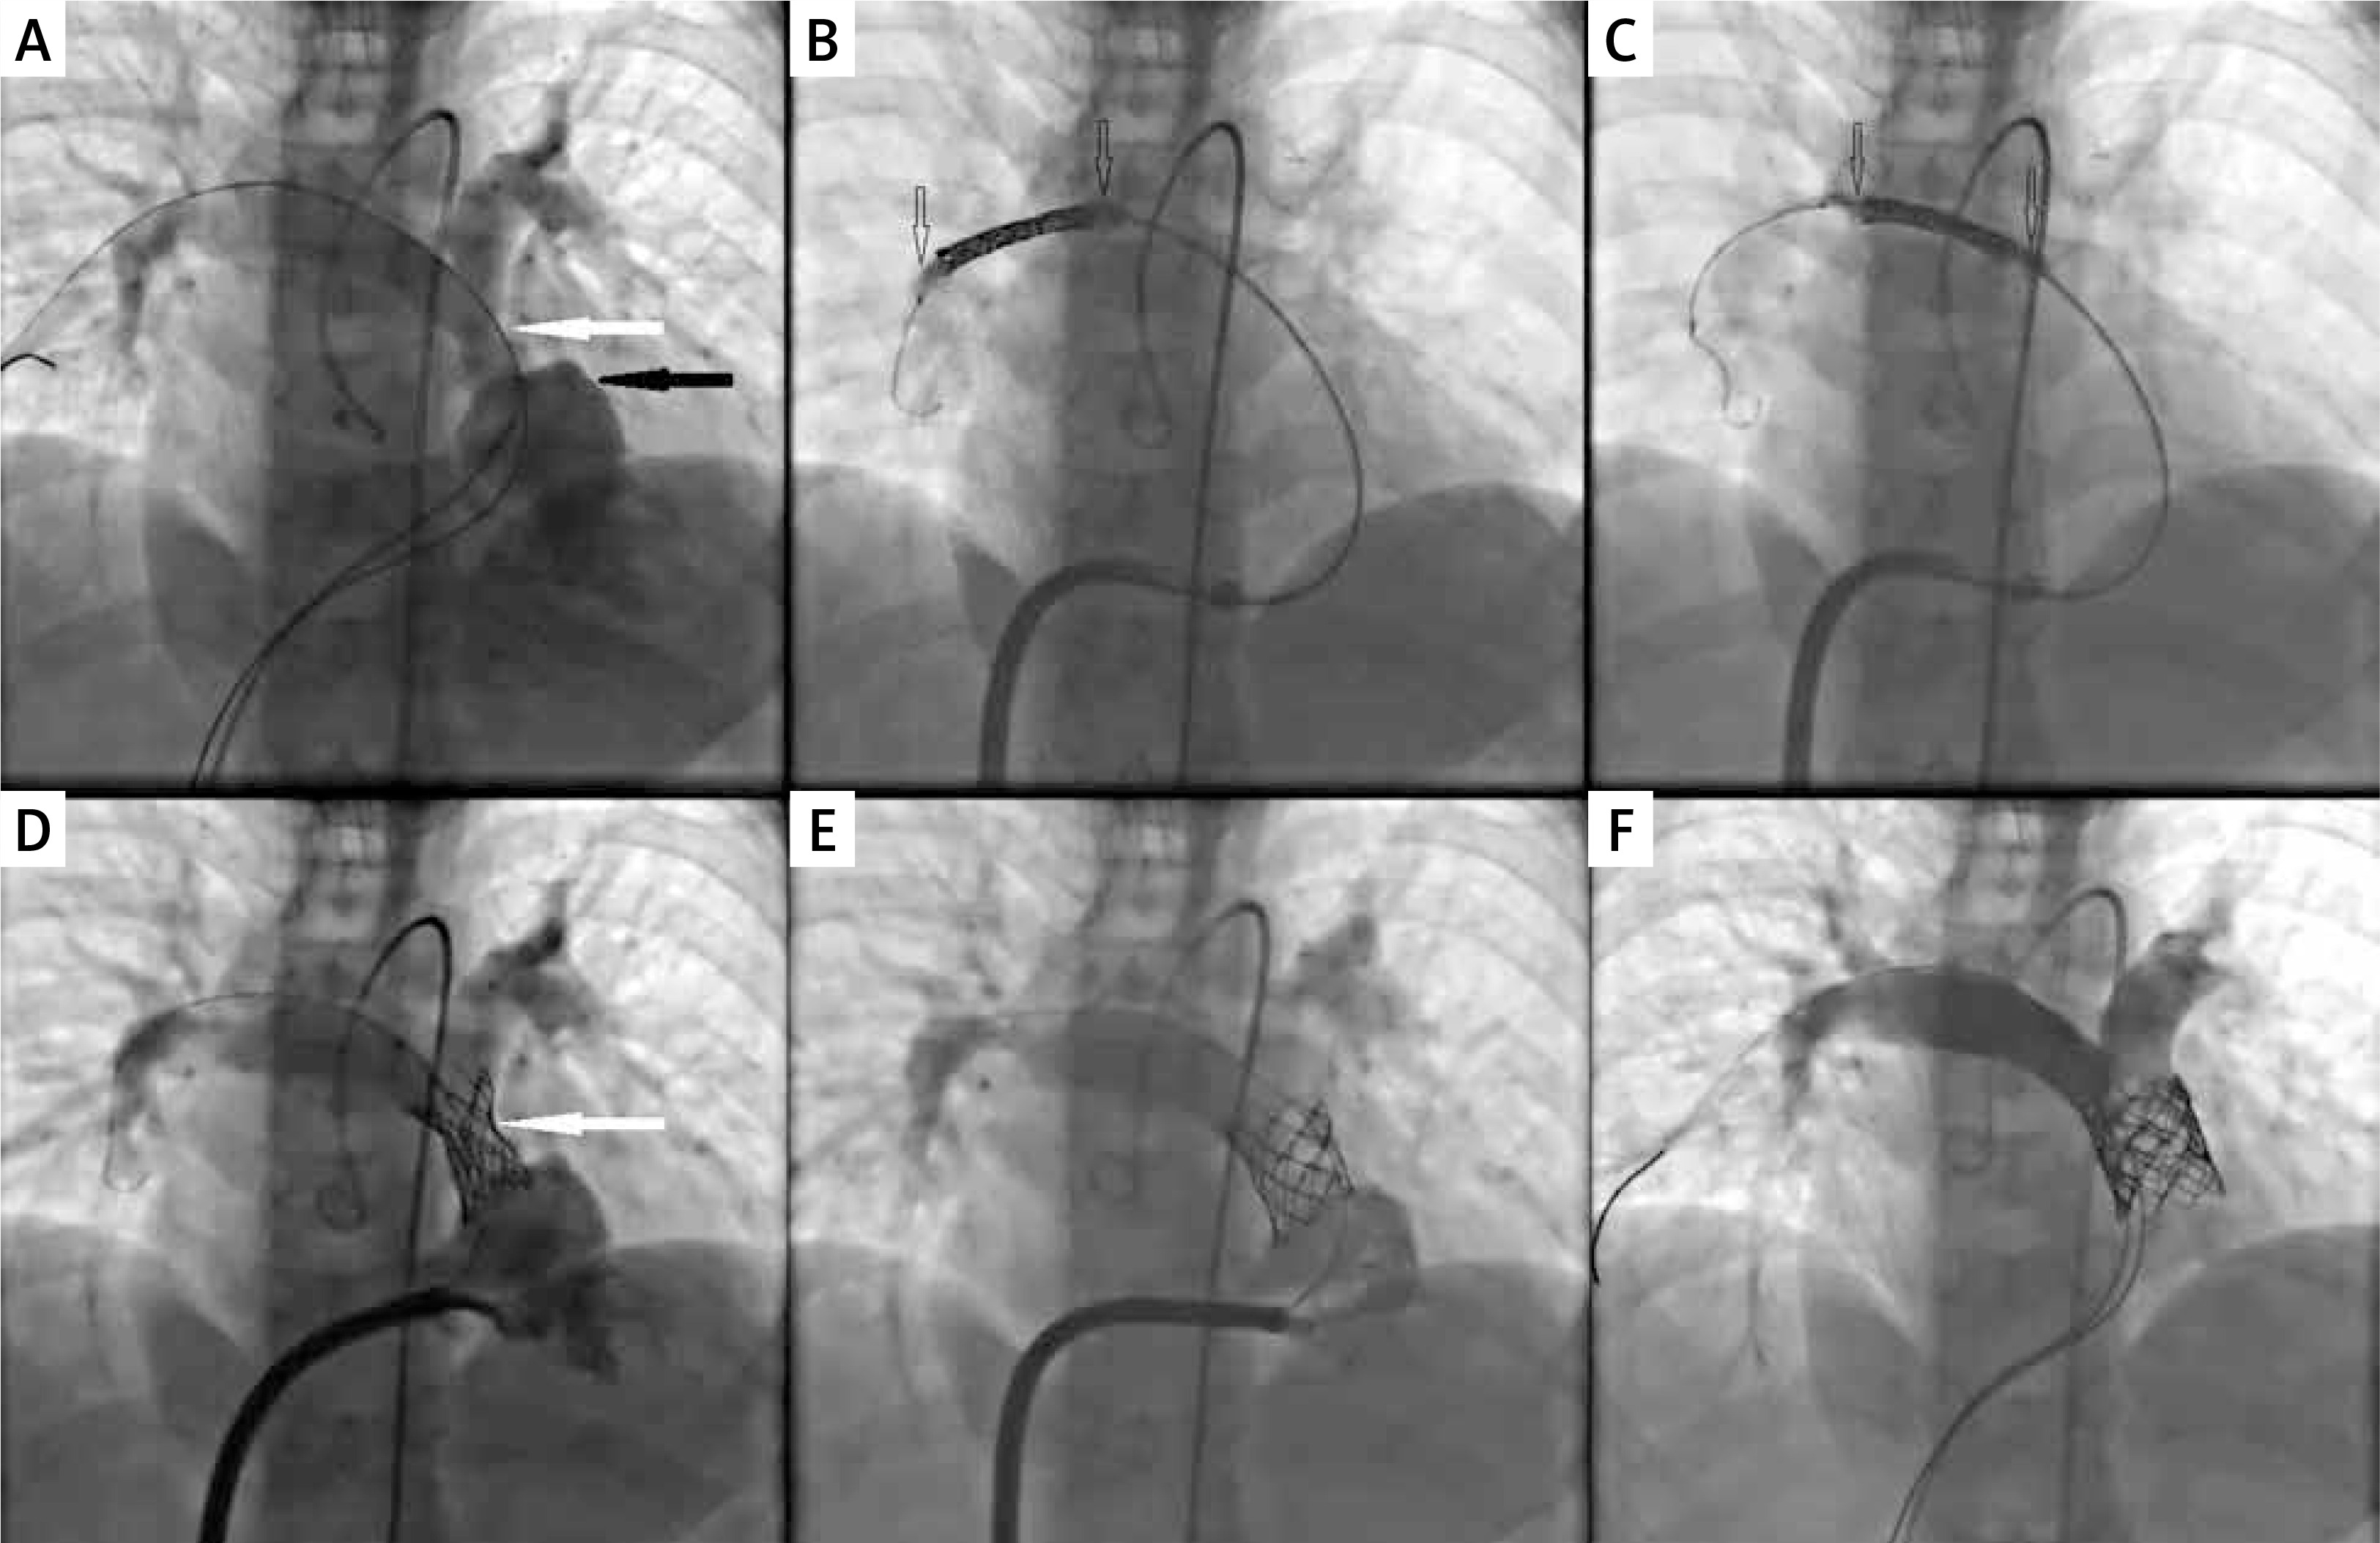

Figure 2

Step-by-step angiographic images of percutaneous pulmonary valve implantation into the narrowed first generation Xeltis Pulmonary Valve (XPV-1) conduit. A – Dilatation of proximal right ventricular outflow track (black arrow) and significant multilevel narrowing in the middle and distal part of the graft (white arrow). B – Non-expanded stent in the distal part of the right pulmonary artery branch with slightly inflated low pressure catheter balloon inside (black empty arrows). C – Stent repositioning on the slightly inflated low pressure catheter balloon (black empty arrows) to the desired position in the graft. D – Control angiography after stent implantation on the low pressure 18 mm catheter balloon in the expected position showed persistent narrowing. E – Control angiography after stent dilatation with a high pressure 20 mm catheter balloon showed total reduction of the narrowing. F – Final angiography after implantation of 22 mm valve and post-dilation with 22 mm high pressure balloon showed no pulmonary regurgitation or narrowing